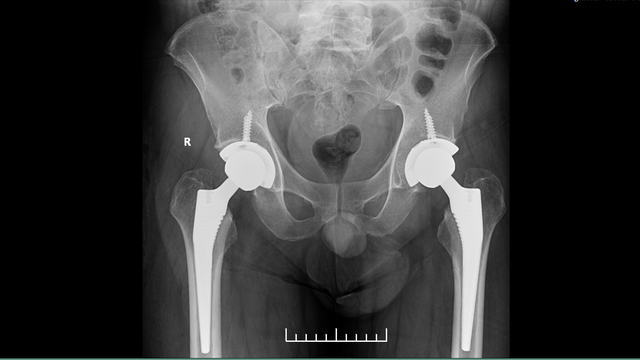

人工髋关节置换是指用生物相容性和机械性能良好的金属或陶瓷材料制成的一种类似人体髋关节的假体,用以置换掉被疾病或损伤所破坏的髋关节,其目的是切除病灶、消除疼痛、矫正畸形,尽可能恢复髋关节的活动与功能。

髋关节置换适应症髋关节骨性关节炎股骨头缺血性(无菌性)坏死类风湿性关节炎晚期先天性髋关节脱位或髋臼发育不良股骨颈骨折:老年患者、骨折移位明显陈旧性股骨颈骨折骨折不愈合或继发股骨头坏死关节成形术失败的病例股骨头、颈部骨肿瘤